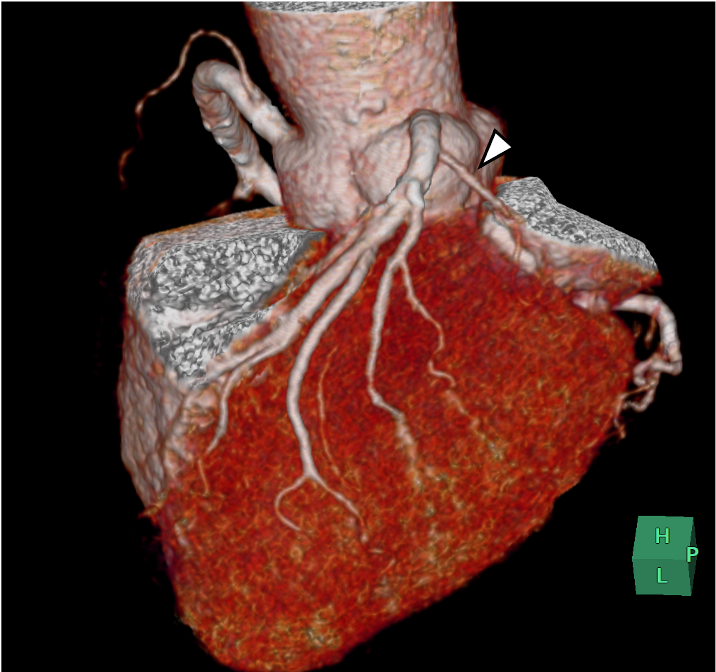

図1.volume rendering(VR)画像

右冠動脈(RCA)は下壁および側壁の一部を広く灌流している.